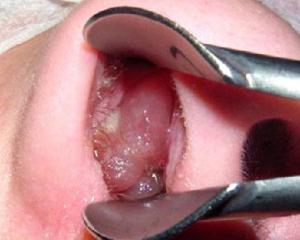

Полипы шейки матки (полипы цервикального канала) — это образования, которые находятся на стенках цервикального канала и растут в его просвет. Они могут находиться как в наружной части зева, где их легко увидеть, так и в верхней части канала. Полипы могут быть как одиночными, так и множественными, образуя полипоз.